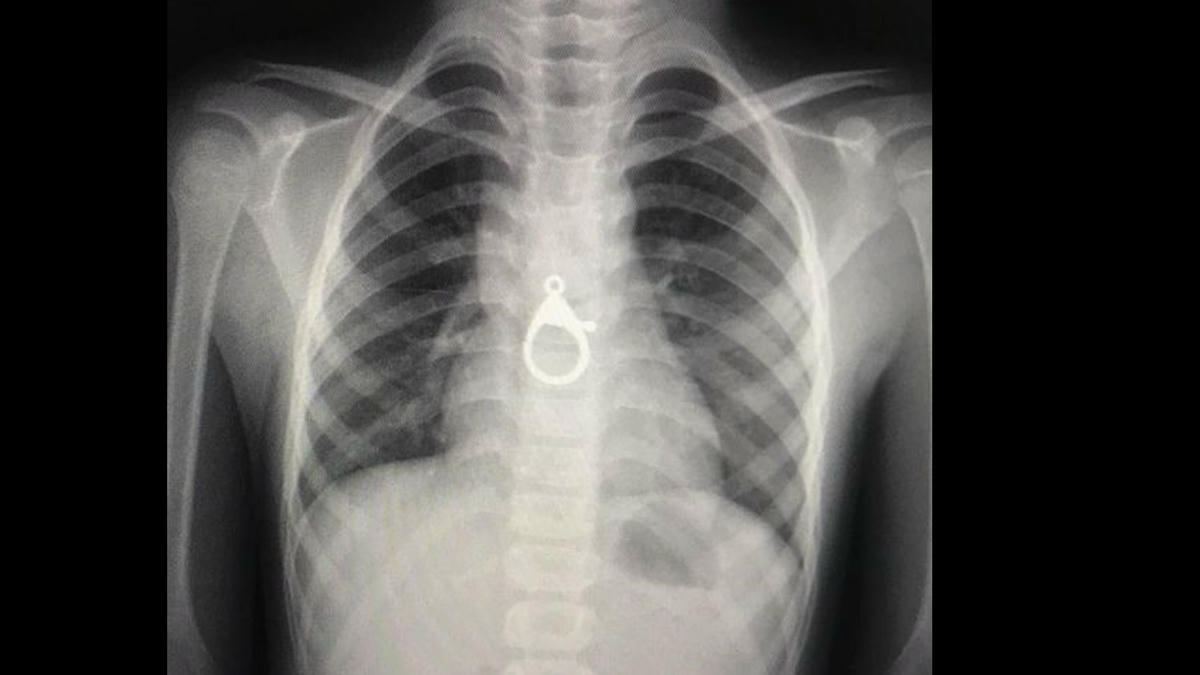

Sau khi tiếp nhận cháu H., các y, bác sĩ đã tiến hành thăm khám và chụp XQ ngực thì phát hiện một dị vật hình móc khóa ở trong vùng ngực cháu H..

Các y, bác sĩ khoa Tai - mũi - họng của bệnh viện đã tiến hành gây mê, nội sọi và gắp thành công 1 móc khóa trong thực quản cháu H. ra ngoài an toàn.